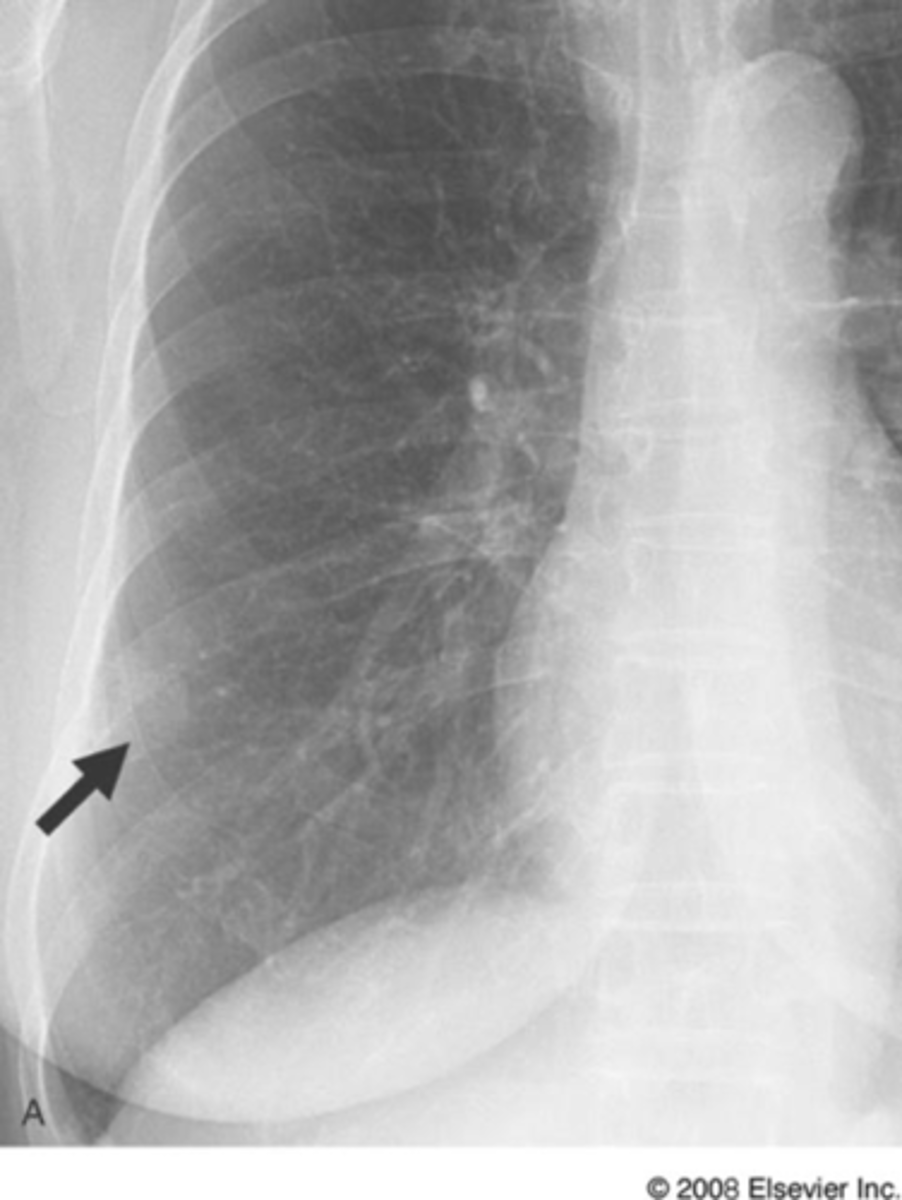

vertebral bodies are lighter (white) than normal on lateral x-ray view

spine sign